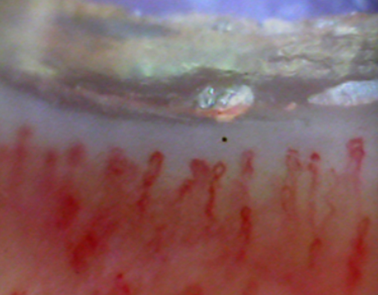

모세혈관 상태를 확인하는 방법 검사는 어려가지지만 제가 추천하는 혈관검사는 조갑주름현미경 검사기기 입니다

손가락을 현미경에 올려놓고 손톱 아래 부분을 관찰하기만 하면 됩니다

당뇨인의 모세혈관 상태를 아래와 이미지를 통해서 좋지 않는 것을 볼 수 있습니다

모세혈관은 길고 쭉 뻗어있으며 색깔은 붉은 빛이 정상 입니다

하지만 혈관이 전반적으로 짧거나 구불하거나 희미하거나 변형이 보이면 안좋은 상태라고 할 수 있습니다